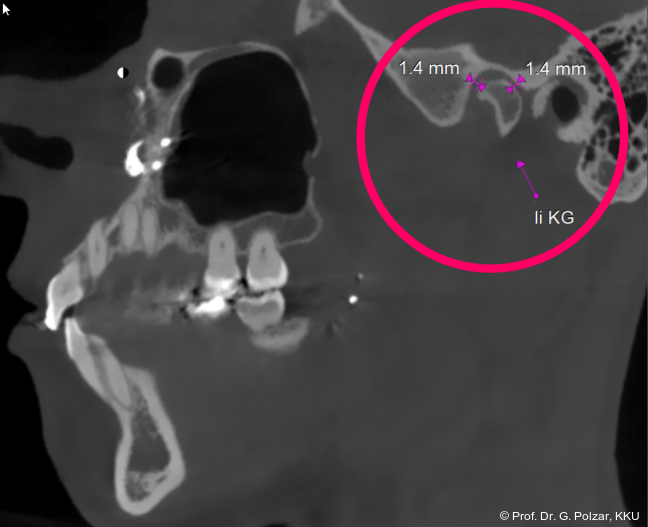

KG-Position: Die 3D-Ansicht im DVT zeigt eine vorverlagerte UK-Position bei neutraler Okklusion (Abb. 4a+b).

Im Sagittalschnitt zeigen beide Kiefergelenke eine deutlich anteriore Position. Der dorsokraniale Abstand betrug rechts 7,0 mm und links 5,8 mm. In der PEP waren sie im lateralen Bereich ca. 1 mm kleiner als in der Mitte der Sagittalprojektion (Abb. 6a–d).

Diese deutlich anteriore Gelenkposition im Neutralbiss ließ den Verdacht auf einen Sunday Bite zu. Das heißt, die Patientin schob den Unterkiefer aktiv nach vorne, um damit schönere Schneidezahnkontakte bzw. eine vermeintlich neutrale Okklusion zu erreichen. Nach mühsamen Lockerungsübungen gelang es der Patientin, auch in die zen­trale Kiefergelenkposition zu wechseln. So zeigte sich das ganze Ausmaß der Malokklusion. In neutraler KG-Position hatte die Patientin eine sagittale Frontzahnstufe von ca. 7 mm mit 1 PB Klasse II-Okklusion im Seitenzahn­bereich (Abb.5a+b, 7a–c).